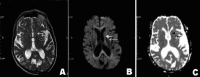

Irreversible chorea as the initial presentation of polycythemia rubra vera in an elderly woman